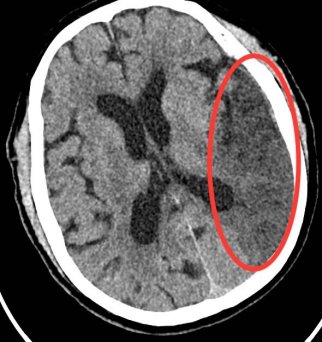

【医讯速览·新闻】第53期:紧急救援 刻不容缓——我院成功救治一名急性大面积脑梗死患者